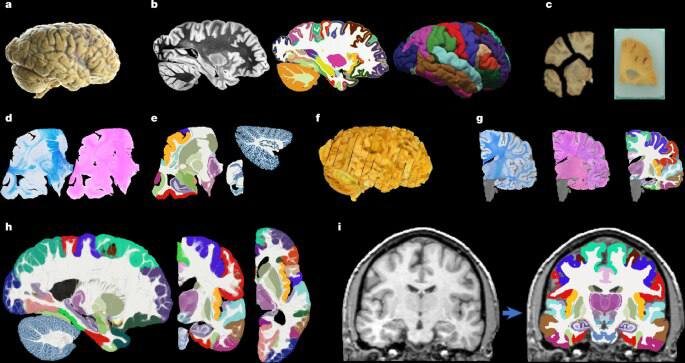

Ученые представили NextBrain — открытый вероятностный гистологический атлас всего человеческого мозга, созданный для более точной сегментации МРТ. Проект объединяет методы искусственного интеллекта, автоматической регистрации и сегментации, чтобы реконструировать мультимодальную серийную гистологию пяти половин человеческого мозга.

В отличие от классических анатомических атласов, NextBrain учитывает вариативность структуры мозга между людьми. Атлас построен как вероятностная модель: он показывает не «средний» мозг, а распределения анатомических особенностей, что особенно важно для нейровизуализации, клинических исследований и разработки медицинских ИИ-моделей.

Ключевая особенность NextBrain — связка микроскопической гистологии и макроскопических МРТ-данных. Это позволяет точнее сопоставлять то, что врачи видят на МРТ-сканах, с реальной тканевой структурой мозга. Такой подход может существенно повысить качество автоматической сегментации, диагностики неврологических заболеваний и исследований работы мозга.

Проект открыт для научного сообщества и рассчитан на использование как в академических исследованиях, так и в прикладных медицинских ИИ-системах. По сути, NextBrain — это новый фундаментальный слой инфраструктуры для нейронауки и медицинского ИИ.